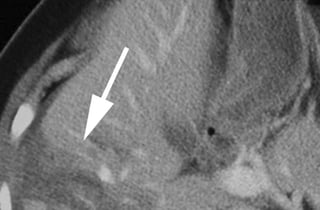

PHOTOS OF CT EVALUATION OF

PREGNANT WOMAN WITH TRAUMA– CT

SCANS DONE AS A PART OF INVESTIGATIONS

DONE IN EMERGENCY --- MATERNAL HEAD

AND ABDOMEN AS PER NEED OF INDIVIDUAL

CASE ---WITHOUT FEAR OF X RAYS

EXPOSURE TO FETUS IN UTERO

PHOTOS OF CTEVALUATION OF PREGNANT WOMAN WITH TRAUMA– CT SCANS DONE AS A PART OF INVESTIGATIONS DONE IN EMERGENCY --- MATERNAL HEAD AND ABDOMEN AS PER NEED OF INDIVIDUAL CASE ---WITHOUT FEAR OF X RAYS EXPOSURE TO FETUS IN UTERO